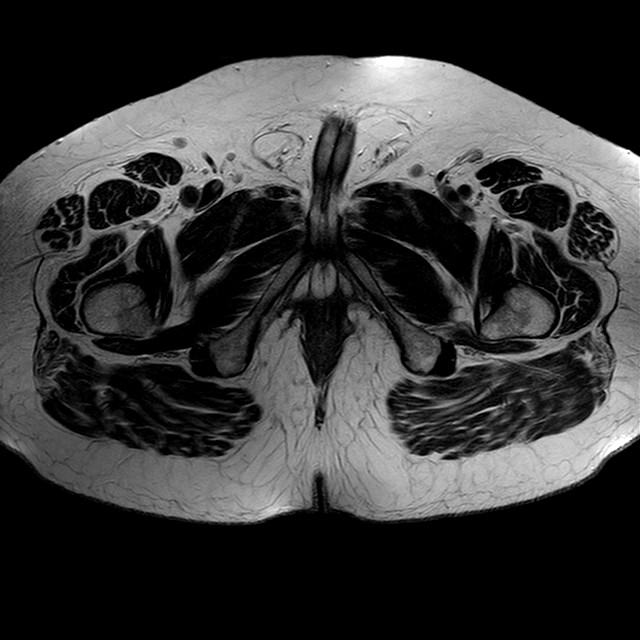

eT2w TSE

Evidenti e simmetriche alterazioni osteofitosiche in regione coxo femorale con riduzione delle rime articolari. Degenerazione completa del cercine glenoideo. Non attuali segni di versamento articolare. Non segni di edema osseo che escludono attuale algodistrofia od osteonecrosi. Lieve e simmetrica riduzione del trofismo della muscolatura glutea.